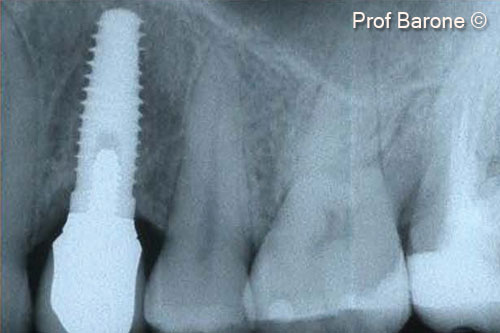

Một bệnh nhân nữ (27 tuổi) có biểu hiện nhiễm trùng cấp tính và mủ từ lỗ rò ở miệng.